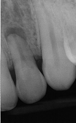

Conventional Treatment with Standard Core Restoration

Non-surgical endodontic treatment with resin core build up